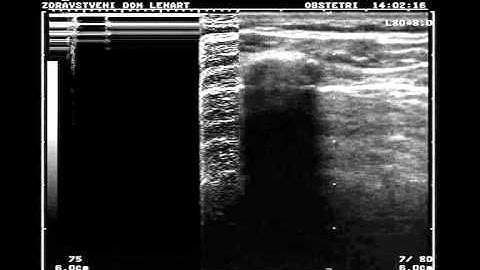

Pneumothorax: Ultrasound Image Interpretation